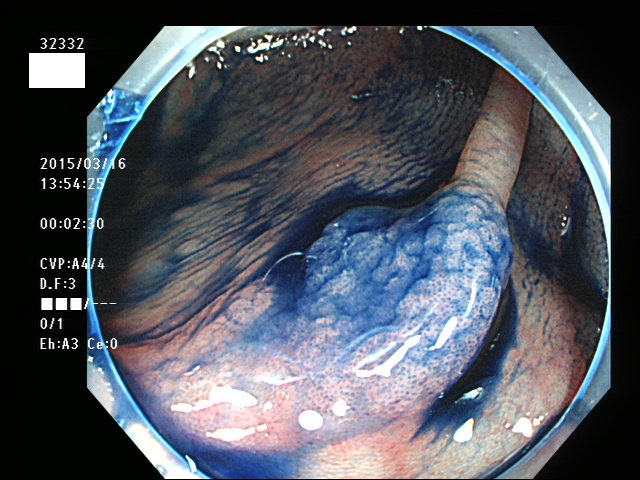

上記100名より抽出した平坦・陥凹型腺腫(=癌化の危険が高いが見落としやすい病変)の内視鏡写真

32300 32301(SSA/Pのみ) 32302(SSA/Pのみ) 32304 32306 32308 32309 32310 32311 32312 32313 32314 32316 32317 32318 32321 32322 32325 32327 32328 32332(SSA/Pのみ) 32334 32335 32336 32338 32339 32341 32342 32343 32345 32348 32349 32350